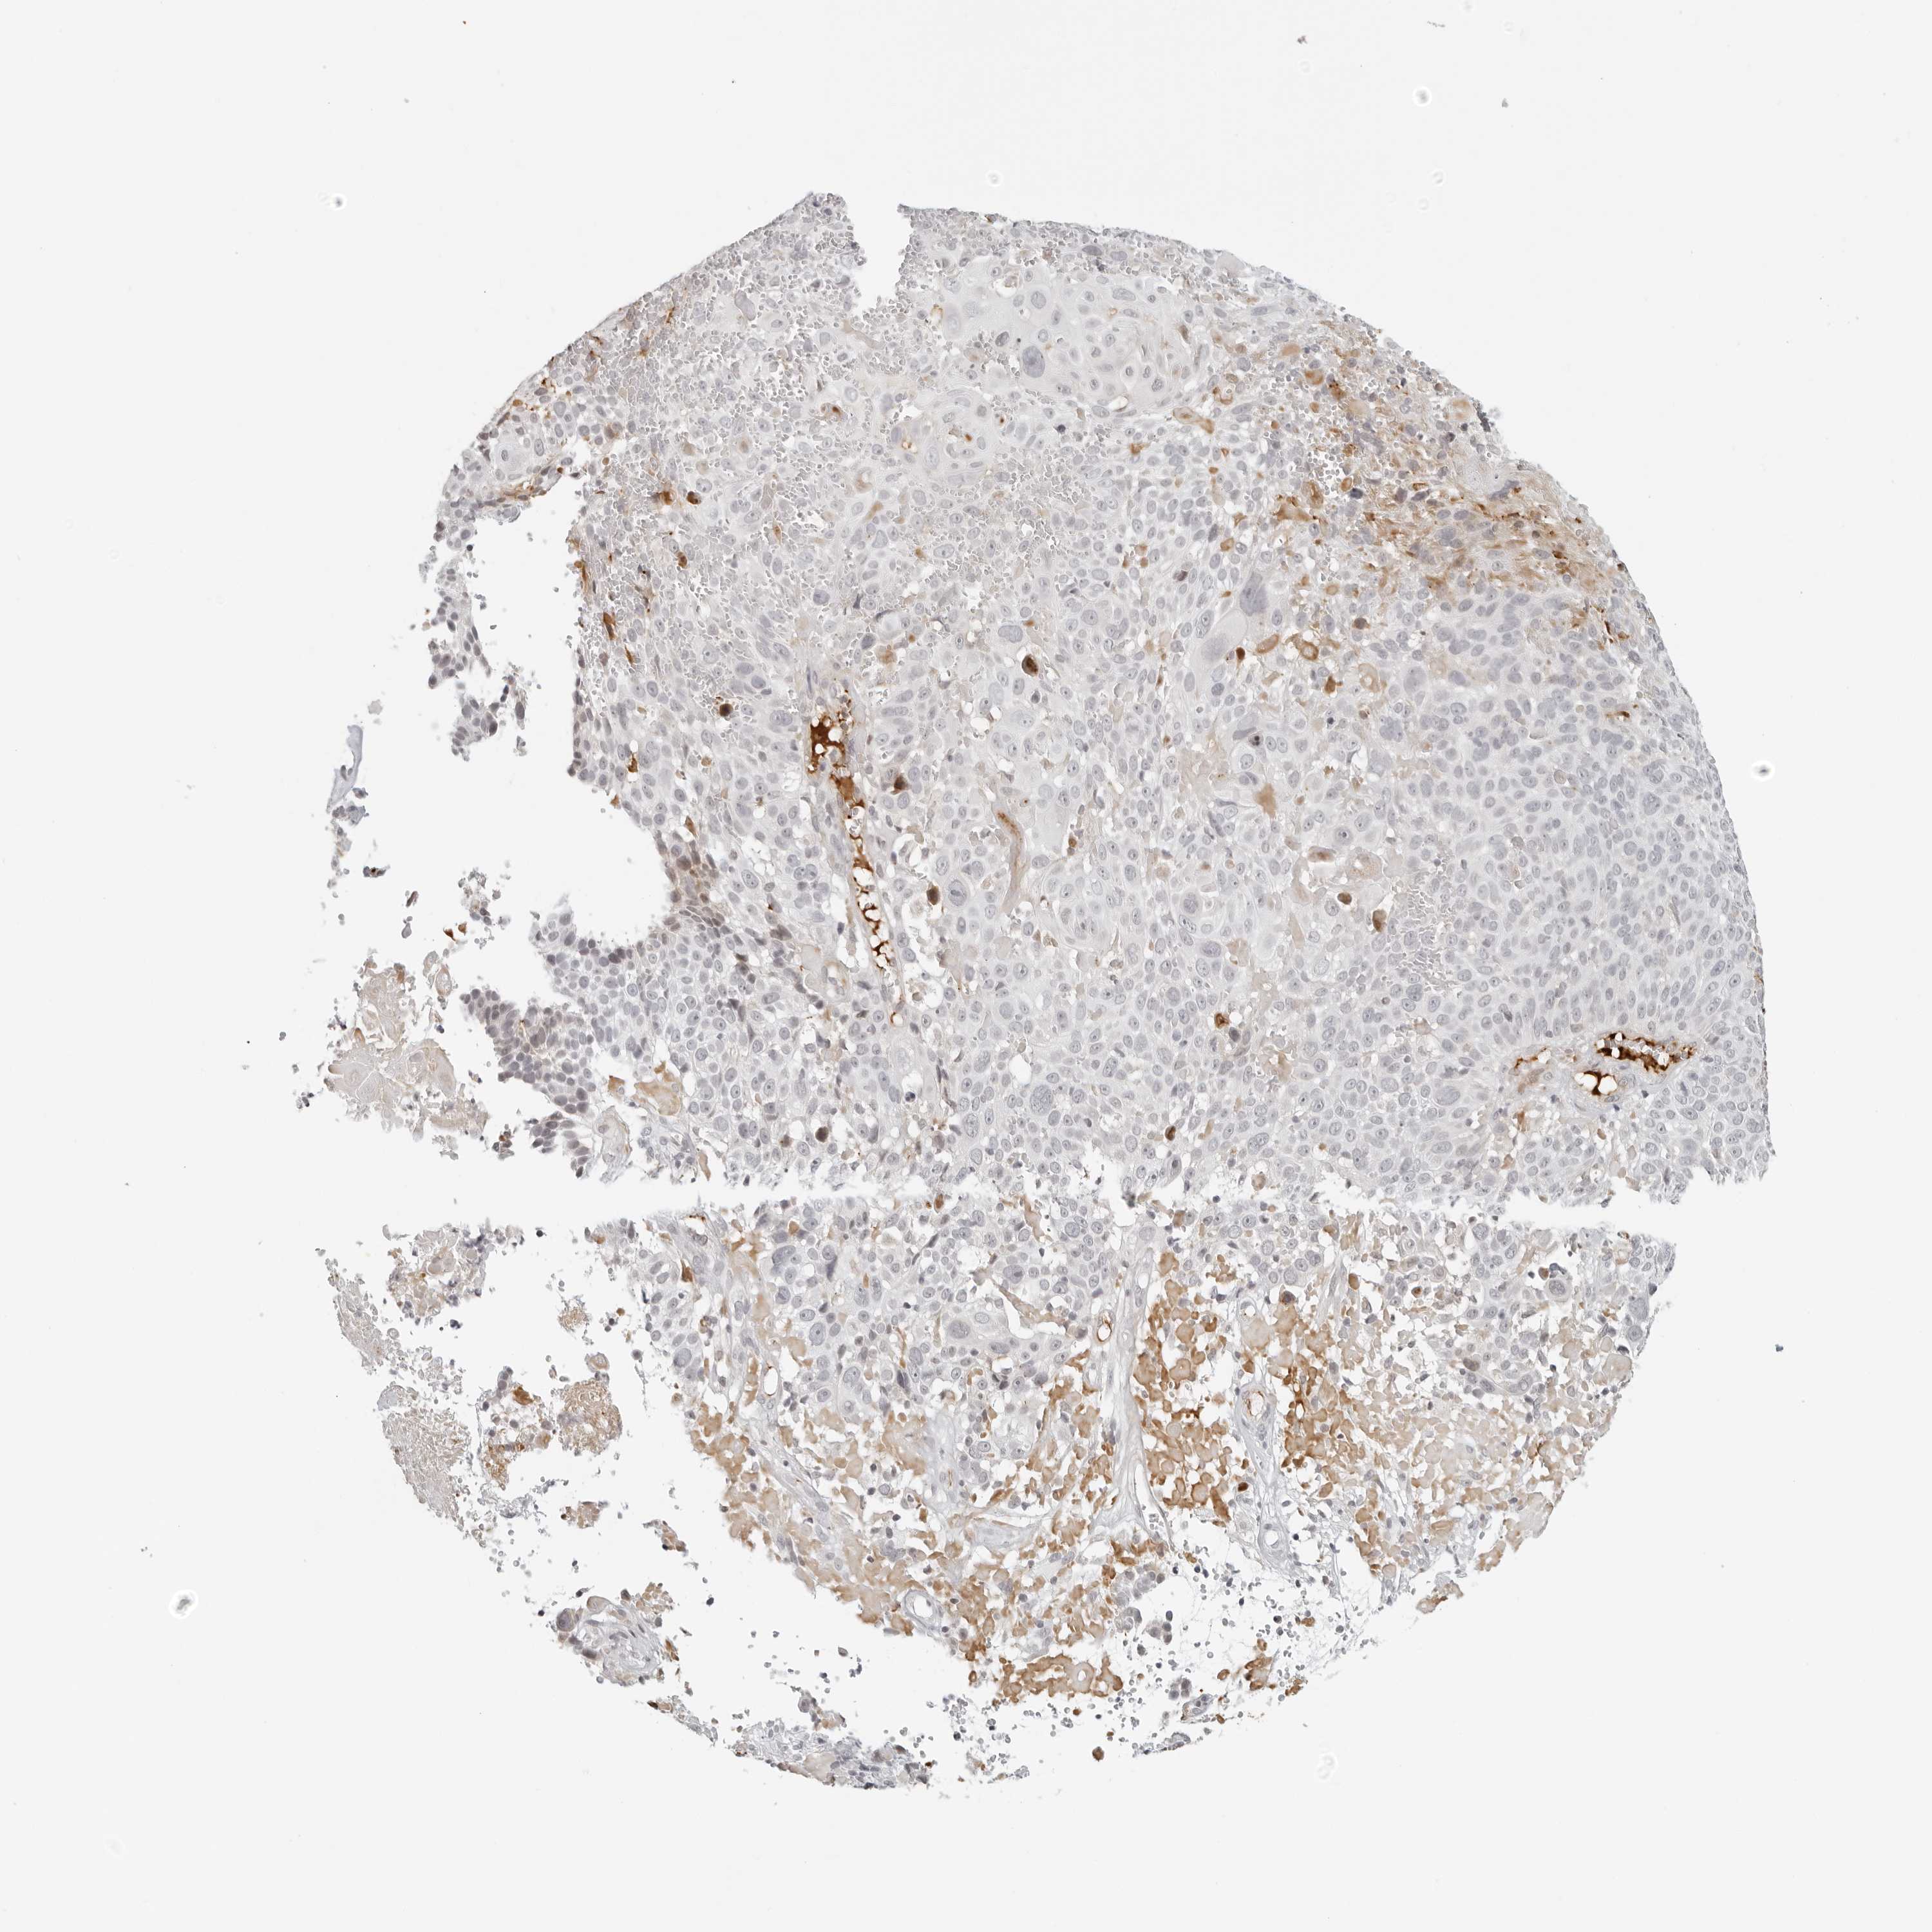

CERVICAL CANCER - Protein expressioni

A mouse-over function shows sample information and annotation data. Click on an image to view it in a full screen mode. Samples can be filtered based on level of antibody staining by selecting one or several of the following categories: high, medium, low and not detected. The assay and annotation is described here.

Note that samples used for immunohistochemistry by the Human Protein Atlas do not correspond to samples in the TCGA dataset.

Antibody stainingi

Antibody staining in the annotated cell types in the current human tissue is reported as not detected, low, medium, or high, based on conventional immunohistochemistry profiling in selected tissues. This score is based on the combination of the staining intensity and fraction of stained cells.

Each image is clickable and will lead to virtual microscopy that enables deeper exploration of all samples and also displays staining intensity scores, fraction scores and subcellular localization as well as patient and tissue information for each sample.

Antibody HPA028507

Staining

High

Medium

Low

Not detected

Intensity

Strong

Moderate

Weak

Negative

Quantity

>75%

75%-25%

<25%

None

Location

Nuclear

Cytoplasmic/membranous

Cytoplasmic/membranous,nuclear

Squamous cell carcinoma, NOS

Adenocarcinoma, NOS